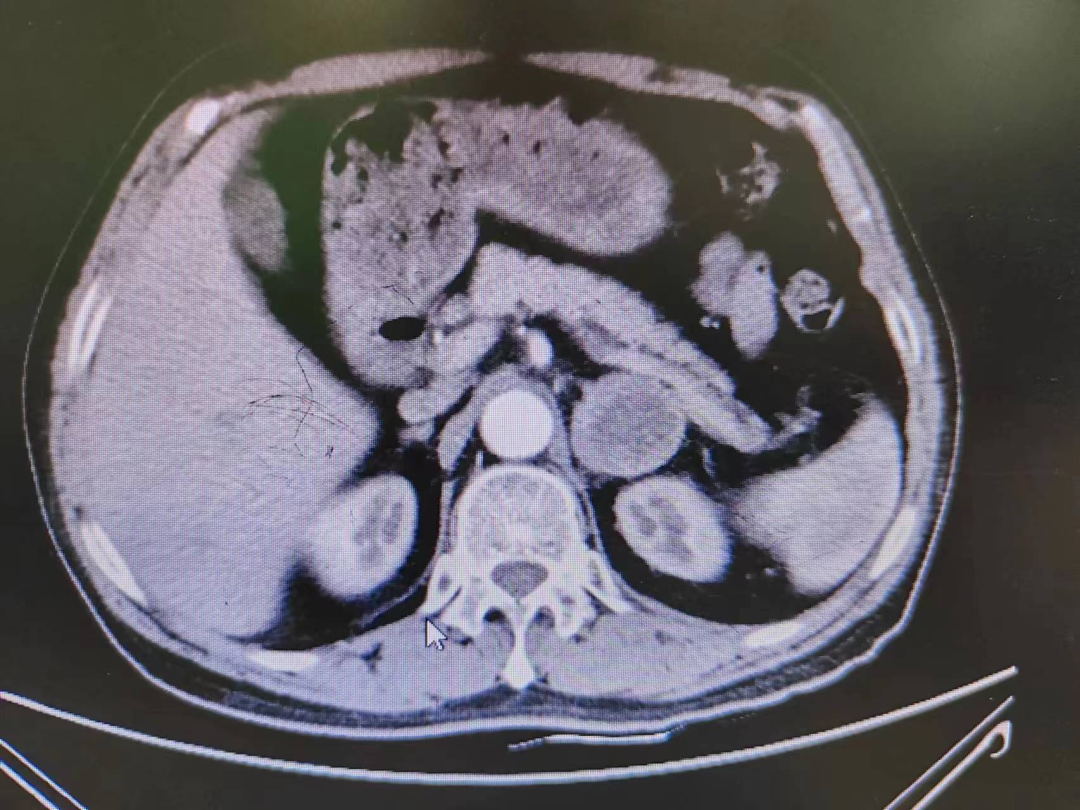

患者熊XX,67岁,因发现头晕、头痛曾多次于外院就诊,到新桥医院就诊完善肾上腺CT考虑嗜铬细胞瘤,既往有高血压病史3年,血压更高达230/120mmHg。我院高新区院区开诊后,患者慕名而来。术前积极完善血尿儿茶酚胺代谢产物(MNS)均明显升高,患者于我院高新区院区及江南院区泌尿外科积极控制血压、心率、血糖,术前充分扩容。

因肿瘤位置位于肾蒂周围,术中触碰肿瘤导致血压明显升高,血压波动较大,肿瘤表面血供丰富,不仅需要手术医生丰富的临床经验和高超的技术水平,也是对医生心理素质、勇气和毅力的严峻考验。

经过泌尿外科医师全体讨论,在进行术前准备2-3周后,再次请多学科讨论评估手术风险,并与患者及家属充分沟通后于6月30日行腹腔镜下左侧肾上腺嗜铬细胞瘤切除术。手术在陈勇主任医师的指导下,由孙伟副主任医师主刀及王传麟医师完成,术中见肿瘤与肾蒂血管周围粘连紧密,与肾动脉、肾静脉分界不清,稍有不慎,可能损伤肾蒂血管可能需要行肾切除术,且分离肿瘤过程中血压波动较大。但在孙伟精准操作及分离下,与麻醉医生和手术护士团队密切配合,经过2小时的手术,顺利切除嗜铬细胞瘤,并保护好肾脏血管及周围组织。术后患者顺利出院,术后血压及血糖控制良好。